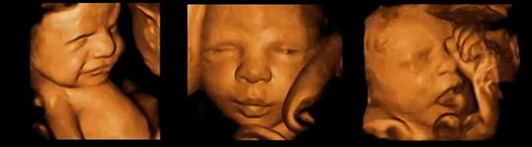

前列,四维彩超超越了传统超声的限制。它除了能够显示出腹中胎儿的实时动态图像外,还能够多方位、多角度的观察宫内胎儿的生长发育情况,对胎儿的体表进行检查,如唇裂,脊柱裂,大脑、肾、心脏、骨骼发育不良等,为早期诊断胎儿先天性体表畸形和先天性心脏疾病提供准确的科学依据。

第二,四维彩超不但能更全面的检测出胎儿的健康状况,而且和过去枯燥乏味的检查过程相比,检查过程更有人情味,更有趣味性。高清四维彩超能够清晰地观察胎儿在妈妈肚子里的一举一动,并能将宝宝的容貌、花拳绣腿的可爱模样给一一记录下来。运气好时还能抓拍到宝宝伸小手摆V字造型,或者揉揉眼睛、打打哈欠等等逗的父母乐不可支的样子,并能够制作成录像成为特别的纪念。